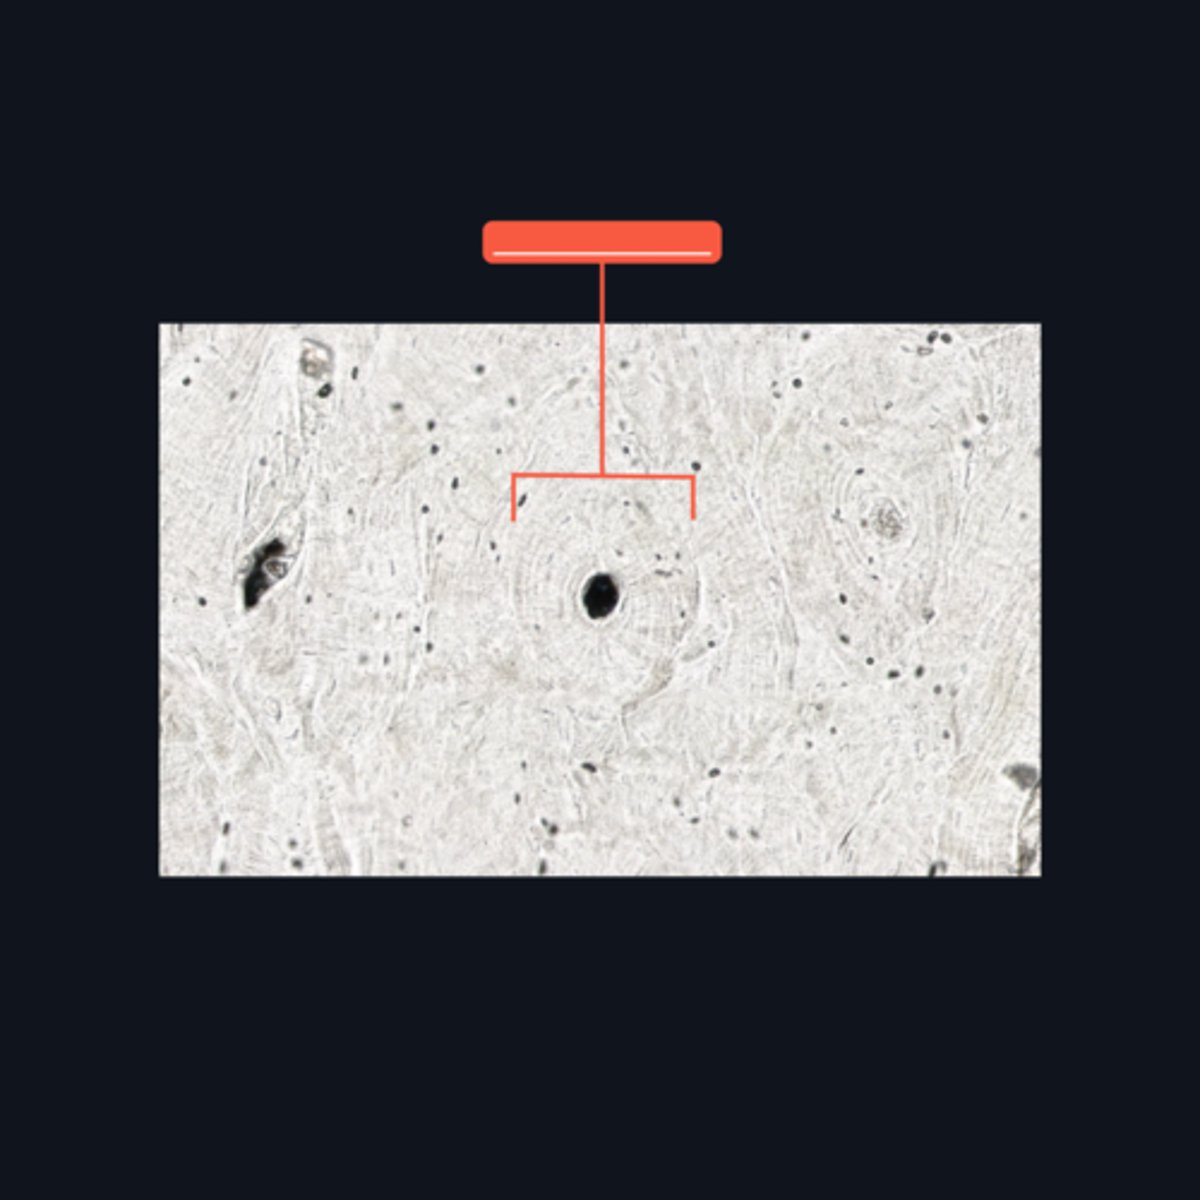

Haversian canal or Canal of Havers

It refers to a longitudinal channel where most of the bone lamellae and their associated osteocytes and lacunae are concentrically arranged

Haversian system or Osteons

This makes up the bulk of compact bone. It consists of several (4-20) bony lamellae with their associated lacunae and osteocytes

Bony lamellae and Lacunae

These are structures found at the ground bone which are concentrically arranged around the Haversian canal